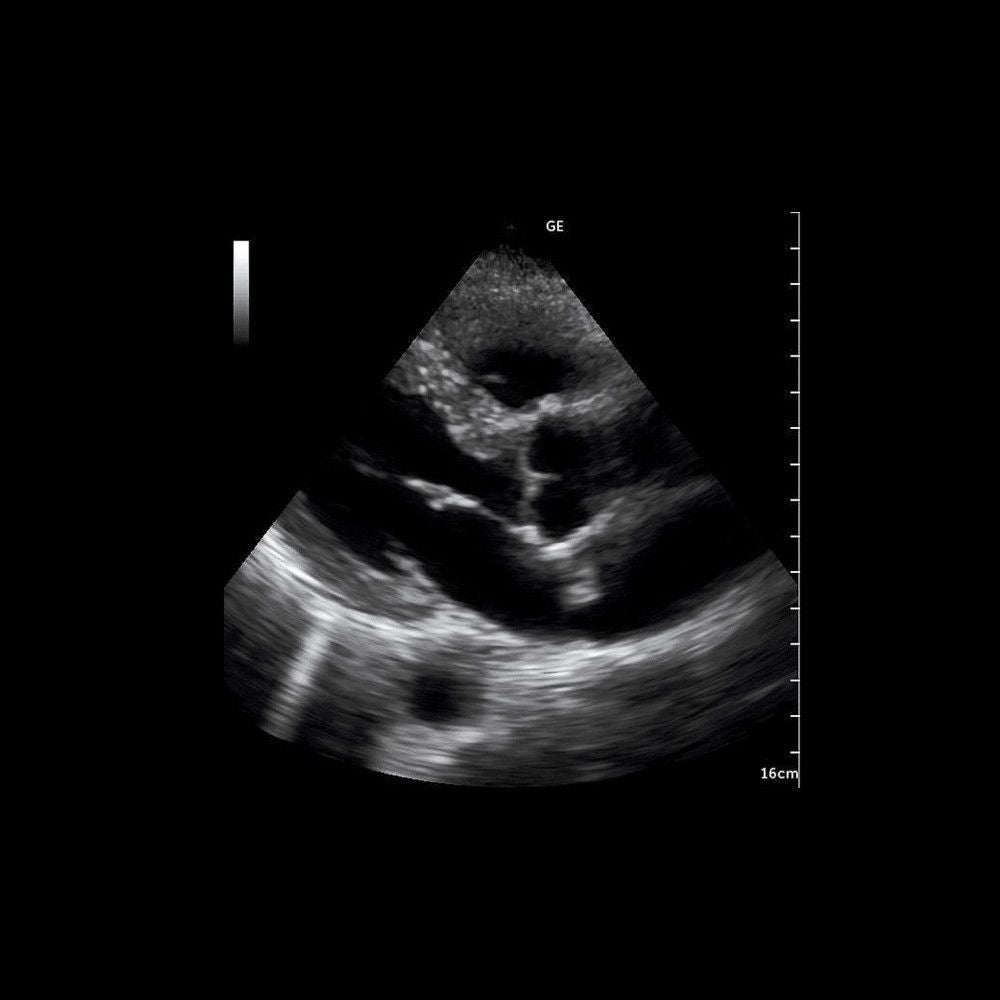

GE Venue 40 Ultrasound with Desk Stand and 12L-SC Probe